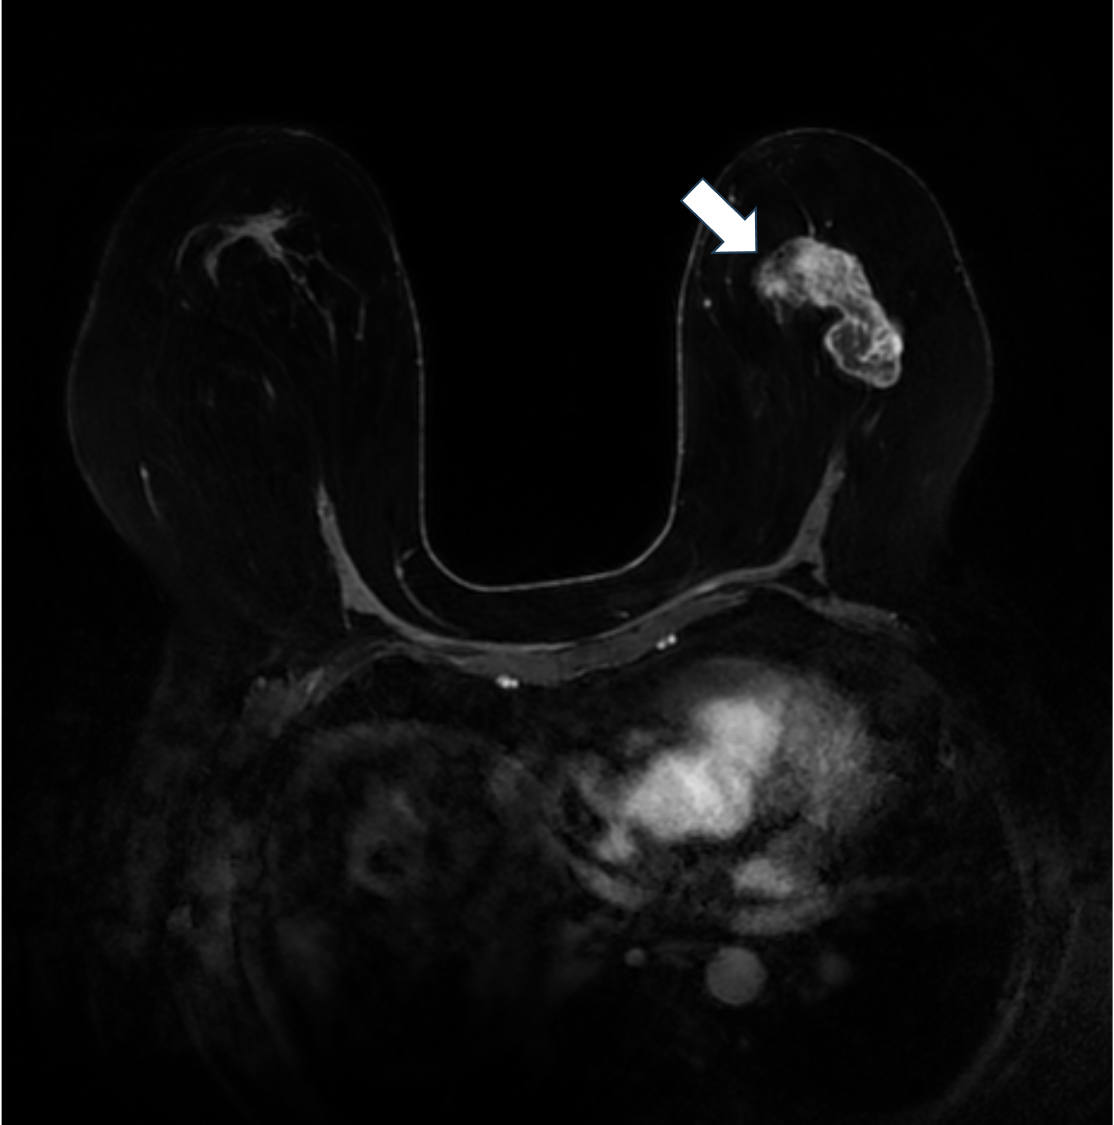

7. 造影後高分解能T1強調画像

造影後高分解能T1強調画像は不整な腫瘤の形状や不均一な内部構造が明瞭に描出されている。乳頭側に強い造影効果がある豊富な充実成分の存在が示唆される。